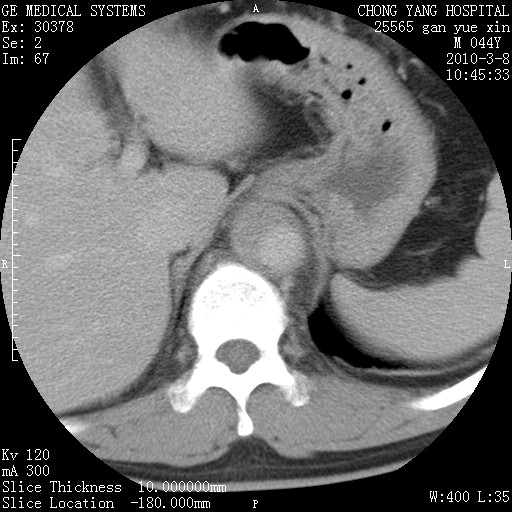

标题: CT24940:主动脉增强,典型病例。 [打印本页]

标题: CT24940:主动脉增强,典型病例。

夹层动脉瘤。

动脉夹层

夹层动脉瘤,典型

主动脉夹层。

动脉夹层的分型:

⒈debakey分型:根据主动脉夹层累及部位,分为三型:ⅰ型:原发破口位于升主动脉或主动脉弓部,夹层累及升主动脉、主动脉弓部、胸主动脉、腹主动脉大部或全部,少数可累及髂动脉。ⅱ型:原发破口位于升主动脉,夹层累及升主动脉,少数可累及部分主动脉弓。ⅲ型:原发破口位于左锁骨下动脉开口远端,根据夹层累及范围又分为ⅲa,ⅲb。ⅲa型:夹层累及胸主动脉。ⅲb型:夹层累及升主动脉、腹主动脉大部或全部。少数可累及髂动脉。

⒉stanford分型:a型:夹层累及升主动脉,无论远端范围如何。b型:夹层累及左锁骨下动脉开口以远的降主动脉。

夹层动脉瘤,少量胸水

夹层动脉瘤;左侧少量胸腔积液。

典型主动脉夹层。